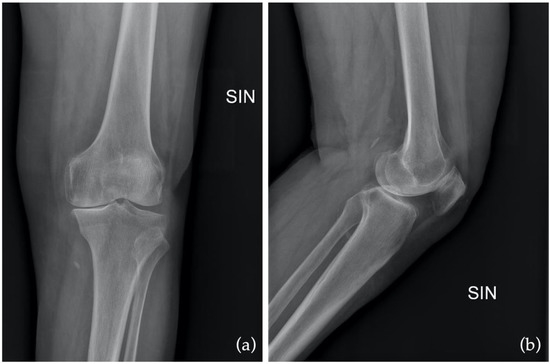

Figure 6.

Preoperative X-ray in anteroposterior (AP) as (a) and in latero-lateral (LL) as (b).